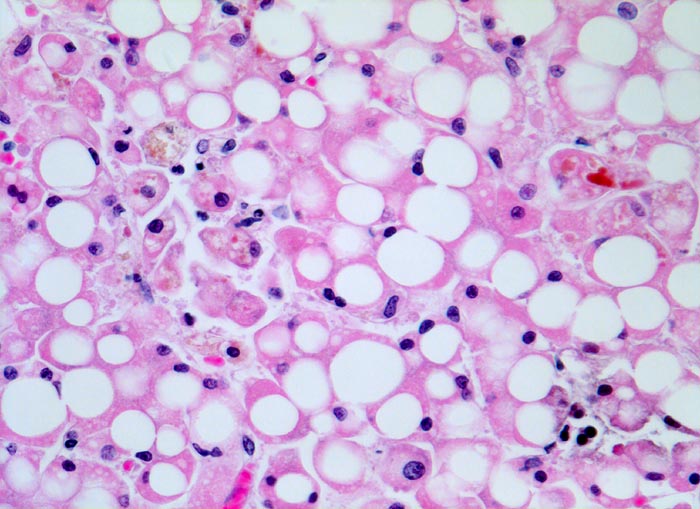

Die Steatose ist der früheste und häufigste pathologische Leberbefund (> 3260) und findet sich bei bis zu 90% der chronischen Alkoholiker. Nach Alkoholkarenz ist sie innerhalb von 3-4 Wochen reversibel. 20-40% der chronischen Alkoholiker entwickeln eine alkoholische Steatohepatitis (ASH). Die Steatohepatitis ist gekennzeichnet durch Schwellung und Ballonierung der Leberzellen, Nachweis von Mallory-Körperchen (> 4947), Apoptosen, perizelluläre Maschendrahtfibrose (> 4950) und überwiegend aus neutrophilen Granulozyten (> 4948) (> 4949) bestehenden Entzündungsinfiltraten. Die Veränderungen sind bei Alkoholkarenz rückbildungsfähig. Bei etwa 50% der Patienten mit Steatohepatitis entwickelt sich eine Leberzirrhose (> 1095).

• Vollständiger feinknotiger zirrhotischer Umbau.

• Floride sklerosierende alkoholische Steatohepatitis: Grobtropfige Verfettung von ca. 50% des Parenchyms.Neutrophile Granulozyten umgeben einzelne Hepatozyten (Satellitose). Wenig Apoptosekörperchen. Zahlreiche Mallory Körperchen und Megamitochondrien. Perivenuläre Maschendrahtfibrose.

• Canaliculäre Cholestase in einem Zirrhoseknoten.